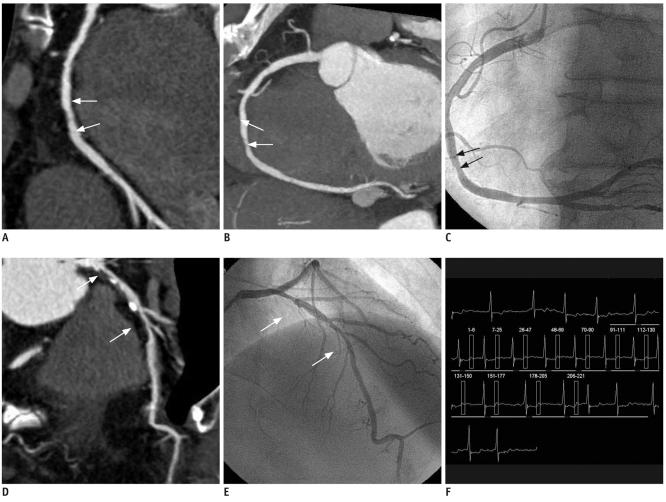

64 层双源 CT 冠状动脉成像在心房颤动患者中的诊断价值:与有创冠状动脉造影的比较。

Diagnostic value of 64-slice dual-source CT coronary angiography in patients with atrial fibrillation: comparison with invasive coronary angiography.

We wanted to evaluate the image quality and diagnostic value of 64-slice dual-source computed tomography (DSCT) coronary angiography in patients with atrial fibrillation (Afib).

MATERIALS AND METHODS

The coronary arteries of 22 Afib patients seen on DSCT were classified into 15 segments and the imaging quality (excellent, good, moderate and poor) and significant stenoses (≥ 50%) were evaluated by two radiologists who were blinded to the conventional coronary angiography (CAG) results. The sensitivity, specificity, positive predictive value (PPV) and negative predictive value (NPV) for detecting important coronary artery stenosis were calculated. McNemar test was used to determine any significant difference between DSCT and CAG, and Cohen's Kappa statistics were calculated for the intermodality and interobserver agreement.

RESULTS

The mean heart rate was 89 ± 8.3 bpm (range: 80-118 bpm). A range from 250 msec to 300 msec within the RR interval was the optimal reconstruction interval for the patients with Afib. The respective overall sensitivity, specificity, PPV and NPV values were 74%, 97%, 81% and 96% for reader 1 and 72%, 98%, 85% and 96% for reader 2. No significant difference between DSCT and CAG was found for detecting a significant stenosis (reader 1, p = 1.0; reader 2, p = 0.727). Cohen's Kappa statistics demonstrated good intermodality and interobserver agreement.

CONCLUSION

64-slice DSCT coronary angiography provides good image quality in patients with atrial fibrillation without the need for controlling the heart rate. DSCT can be used for ruling out significant stenosis in patients with atrial fibrillation with its high NPV for detecting in important stenosis.